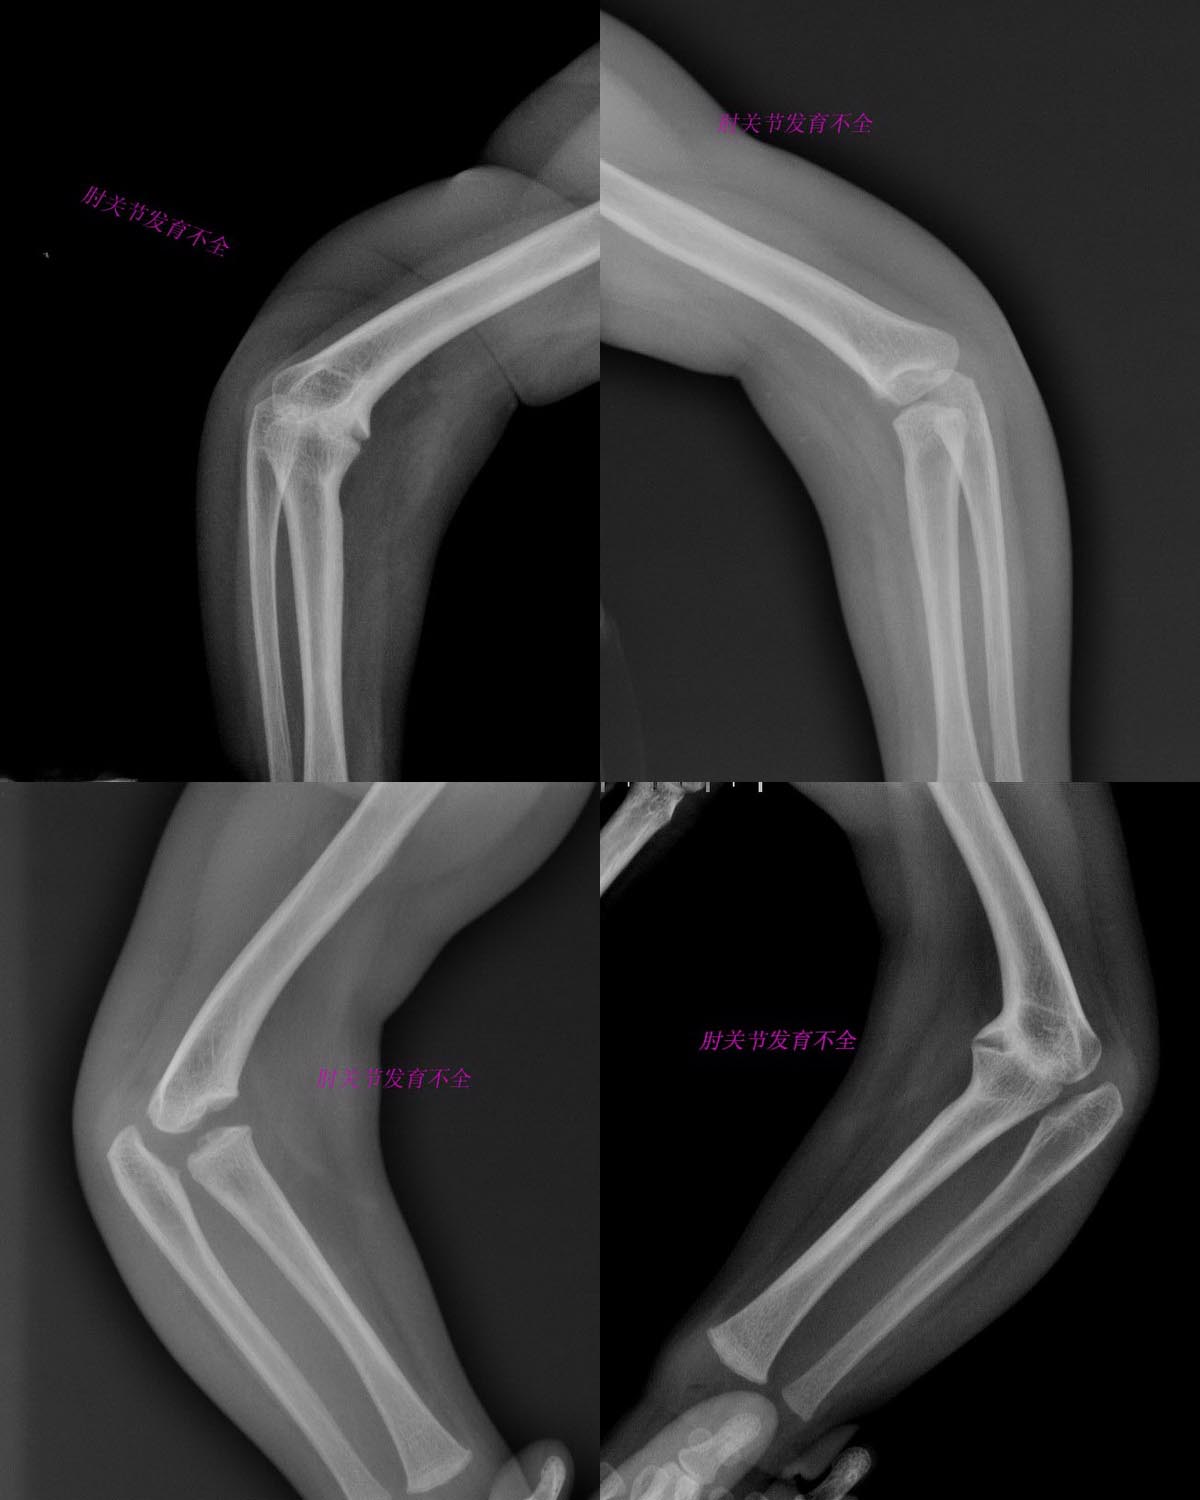

以下是引用余辉在2009-3-30 22:20:00的发言:[br]双侧肱骨小头骨骺未出现,前外侧见异常骨性关节面形成,桡骨近端肥大,桡骨与肱骨异常关节面对合,尺骨滑车切迹稍浅.[br]考虑肱骨远端骨骺发育不良继发双肘发育不良[emb5][br][br][本贴已被 余辉 于 2009-3-30 22:22:27 修改过]

以下是引用随光逐影在2009-3-31 17:21:00的发言:[br]支持 双肘关节发育畸形。

以下是引用拾荒者在2009-4-1 21:51:00的发言:[br]双肘关节发病,干骺端增宽,接触面有增生,临床无压痛,考虑神经营养性关节病或干骺发育不良。